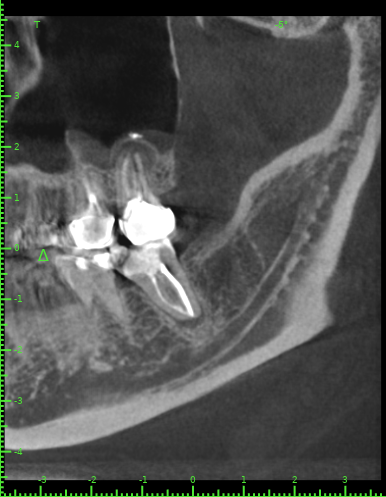

Katya88 Опубликовано 28 июля, 2021 Поделиться Опубликовано 28 июля, 2021 Мой стоматолог терапевт советует удалить, так как там кисты, а ортопед советует найти того, кто займется лечением. КТ прилагаю https://drive.google.com/file/d/1Z-neEH63BszTXxa8bAOG1tgsrIrsqrVK/view?usp=drive_web Ссылка на комментарий

Женька Опубликовано 28 июля, 2021 Поделиться Опубликовано 28 июля, 2021 2.6 2.7 3.7 На 3.5 и 1.5 стоит обратить внимание 1.5 1 Ссылка на комментарий

Женька Опубликовано 28 июля, 2021 Поделиться Опубликовано 28 июля, 2021 54 минуты назад, Katya88 сказал: 1.5 менять коронку как минимум снять существующую конструкцию и посмотреть клинически на зуб(ы). 1.5 на КТ выглядит удручающе. По остальным, я бы поддержал ортопеда и попытался зубы сохранить. Пусть коллеги меня поправят. 1 1 Ссылка на комментарий